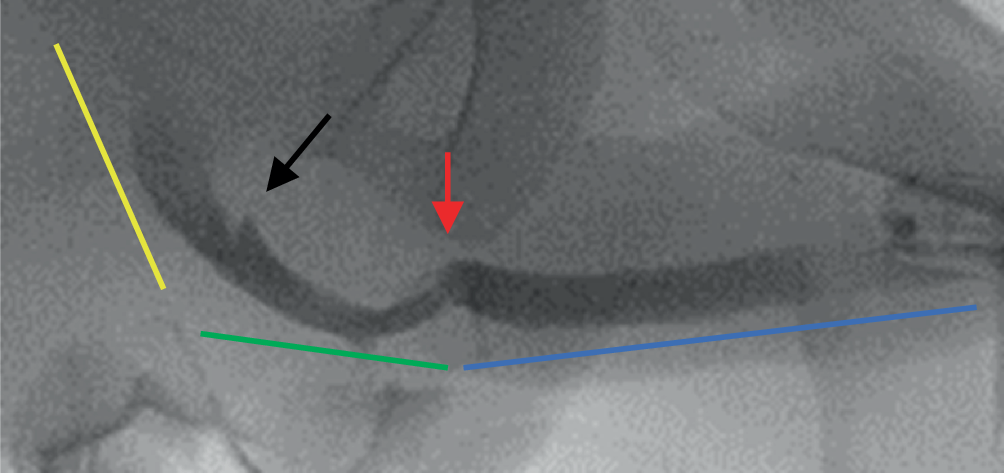

Die Rekonstruktion der Urethra des Neophallus bedingt freie Lappenplastiken mit mikrochirurgischen Gefässanastomosen und vielen Anastomosen- und Tubularisierungsnähten. Durch beides kann die Durchblutung des Gewebes erheblich beeinflusst werden und durch eine daraus resultierende Ischämie zu Fisteln und/oder Strikturen führen. Urethrastrikturen treten in 25–58 % und urethrokutane Fisteln in 22–75 % nach Phalloplastik auf [510]. Die Urethra des Neophallus kann im Wesentlichen in 4 Abschnitte eingeteilt werden: die originäre feminine Urethra, die fixierte Urethra (Pars fixa), die penoidale Urethra (Pars pendulans) und den Neomeatus (Abb. 5). Anastomosen finden sich jeweils zwischen der originären und der fixierten Urethra sowie der fixierten und der penoidalen Urethra. Die fixierte Urethra besteht aus gestielten Läppchen der Labia minora, das Gewebe ist in der Regel weich und elastisch, und es fehlt ein stabilisierendes, umgebendes Corpus spongiosum. Damit kann dieser Anteil der Urethra oft auch etwas dilatiert sein, insbesondere bei vorgeschalteten Strikturen. Die Pars pendulans wird in der Regel durch den freien Radialislappen gebildet, ist von Plattenepithel ausgekleidet und von Binde- und Fettgewebe umgeben. Ein Corpus spongiosum fehlt auch hier, jedoch ist dieser Anteil in der Regel weniger elastisch. Die Strikturen treten zu 15 % im Neomeatus, zu 24 % in der Pars pendulans, zu 13 % in der Pars fixa und zu 41 % in der Anastomose zwischen Pars fixa und Pars pendulans auf [11]. Strikturen sind in 8 % multifokal.

Abb. 5

Retrogrades Urethrogramm einer transmaskulinen Urethra: originäre feminine Urethra (gelb), Pars fixa (grün), Pars pendulans (blau), Anastomose zwischen Pars fixa und Pars pendulans (roter Pfeil), Anastomose originäre Urethra und Pars fixa (schwarzer Pfeil). (Mit freundl. Genehmigung, ©Feicke, Universitätsspital Basel, alle Rechte vorbehalten)